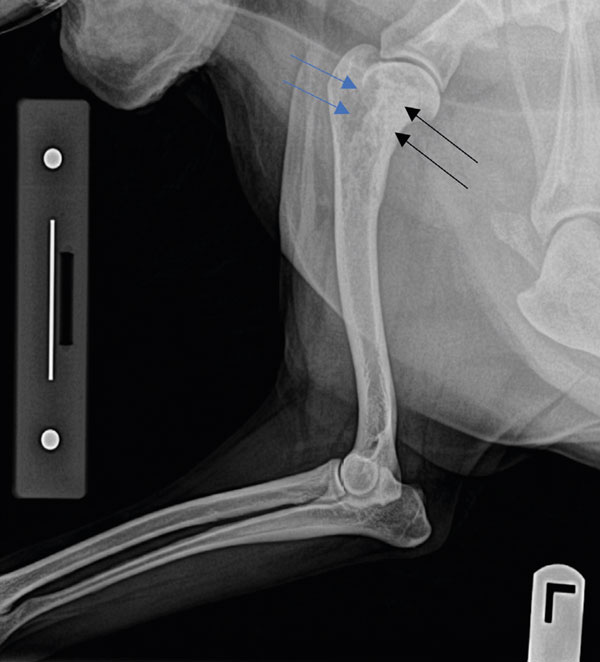

A 12-year-old, female entire Collie presented with a four-week history of progressive left forelimb lameness which only partially and transiently responded to rest and anti-inflammatories. On clinical examination, a severe, almost non-weight-bearing left forelimb lameness was confirmed at a walk, pain was elicited on palpation of the left proximal humerus, and mild-to-moderate muscle atrophy was present in the left shoulder region. No significant abnormalities were detected on haematology and biochemistry panels. A radiographic study of the left forelimb showed the presence of a single cortico-trabecular bone lesion in the proximal humerus, characterised by a mixed lytic and proliferative pattern and a ‘sun-burst’ periosteal reaction (Figure 1). Given the signalment, clinical signs, radiographic characteristics and location of the lesion, a pre-emptive diagnosis of appendicular osteosarcoma was made. Survey radiographs of the thorax showed no evidence of detectable metastatic disease at the time of diagnosis.

Figure 1: A focal, ill-defined, poorly marginated cortico-medullary bony lesion and a “sunburst” periosteal reaction were identified in the left proximal humerus. This lesion shows a mixed lytic (blue arrows) and proliferative (black arrows) pattern.